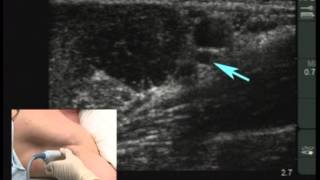

Видео техники эпидуральной анестезии Техника техники эпидуральной анестезии